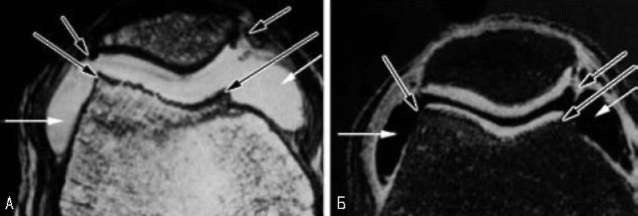

Рис. 7.38. ОА ПФВ суглоба. Аксіальні Т2-ОБ-зображення: А — суглобовий хрящ погано візуалізується; Б — техніка вирахування переносу намагніченості дозволяє чітко продемонструвати суглобовий хрящ. Обидва зображення виявляють формування остеофітів по краях суглоба (чорні стрілки) і надлишкову кількість синовіальної рідини — випіт (білі стрілки)